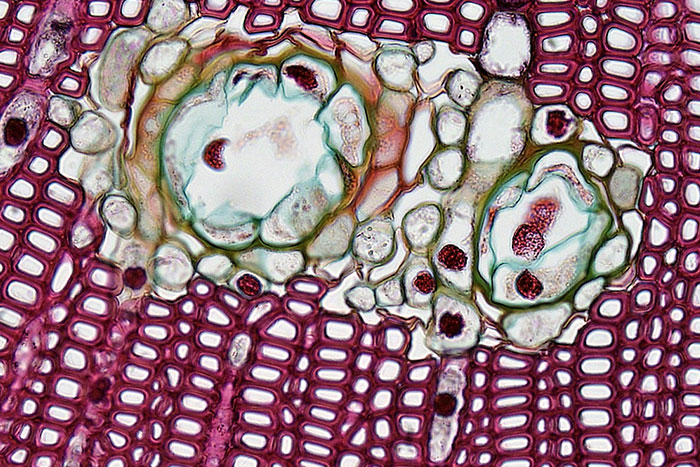

#11

There are so many wild things living in the microbiome of a human's skin. Demodex are a great example; little mites that live near human hair follicles. They look horrific and they feed off of sebum, sweat, dead skin etc.

Many things are localized too; the things living in your eyelash follicles are not the same as the ones living on your elbows. We're a whole universe, and even our skin is colonized by bizarre little f*****s

Edit; a lovely little quote I found online, about Demodex

"When you sleep, the mites come out of your skin’s pores, mate, then go back into your skin to lay eggs."

Sexy.

The eyelash mite lives mainly on the human eyelash and is an 8 legged parasite that eats skin and oil. They stay hidden in the hair follicles during the day and emerge at night to eat, lay eggs and excrete waste. And that is why you should wash your face in the morning.

Image credits: RandomNameGenFail003